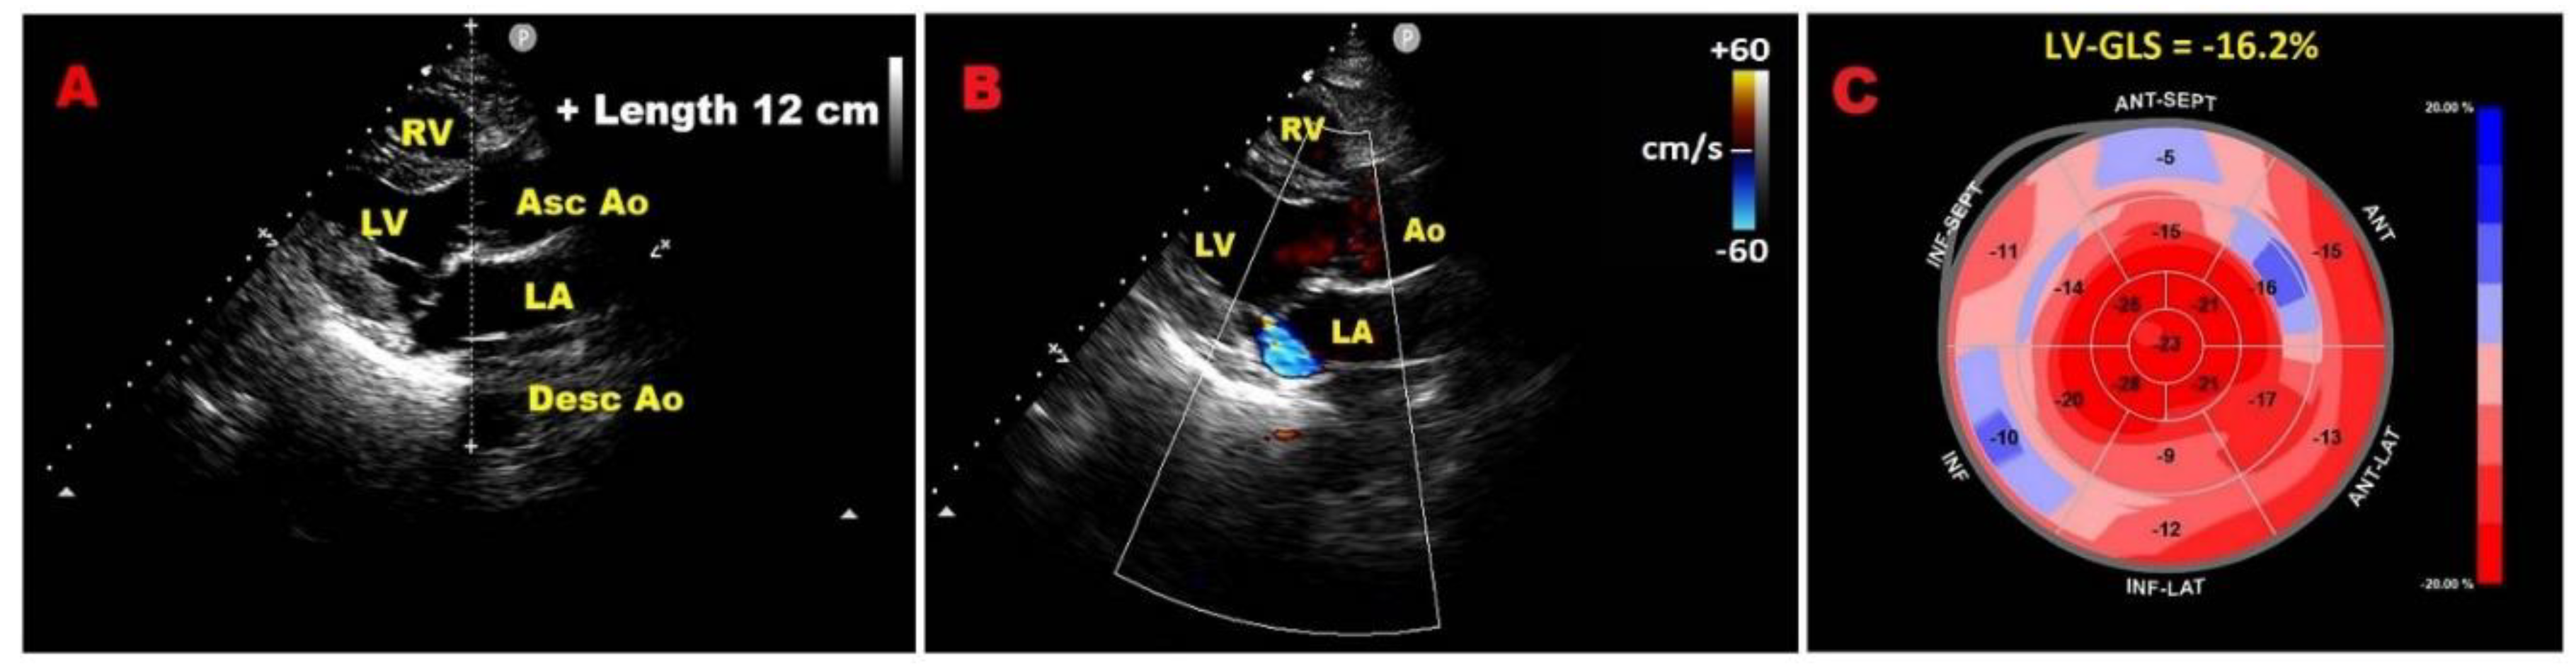

3.1. Left ventricular global longitudinal strain

7.1. Modified Haller Index

7.2. Relationship between chest wall conformation and MAD distance in PMR with MVP